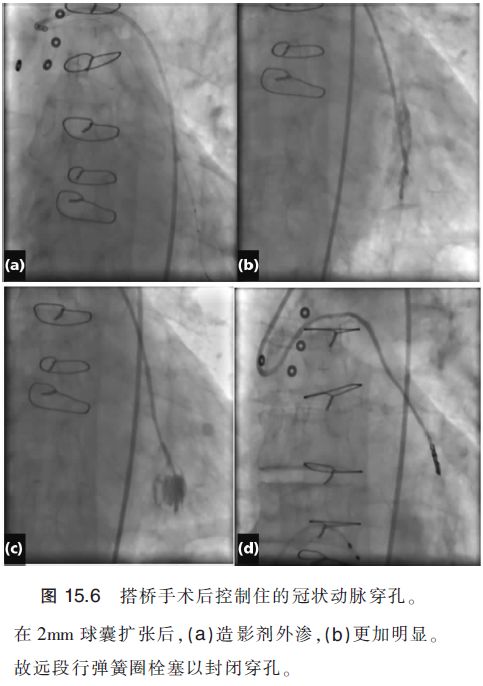

延长球囊扩张治疗,在一些幸运的情况下,可能会使组织瓣永久地覆盖穿孔病变而解决问题。然而,对于严重撕裂来说,覆膜支架是一项很好的选择。对之前有搭桥史的患者来说,PCI术后罕见心包填塞,由于在搭桥中,心包打开并移除,瘢痕组织形成,故穿孔大多局限可控,多见肌间或纵隔内出血而非明显出血或心包积液(图15.6)。如果有覆膜支架,大型穿孔可以被成功处理。由于聚四氟乙烯(PTFE)覆膜支架尺寸较大,故近端节段需预扩,导引导管位置调整好,且需额外的buddy导丝。操作手工皱缩的聚四氟乙烯覆膜支架不应过分用力,因为其可能与球囊滑脱而远端栓塞。遗憾的是,目前的PTFE覆膜支架只有有限的活动性,且尺寸较大,需8F指引导管,尺寸均大于3.0mm。